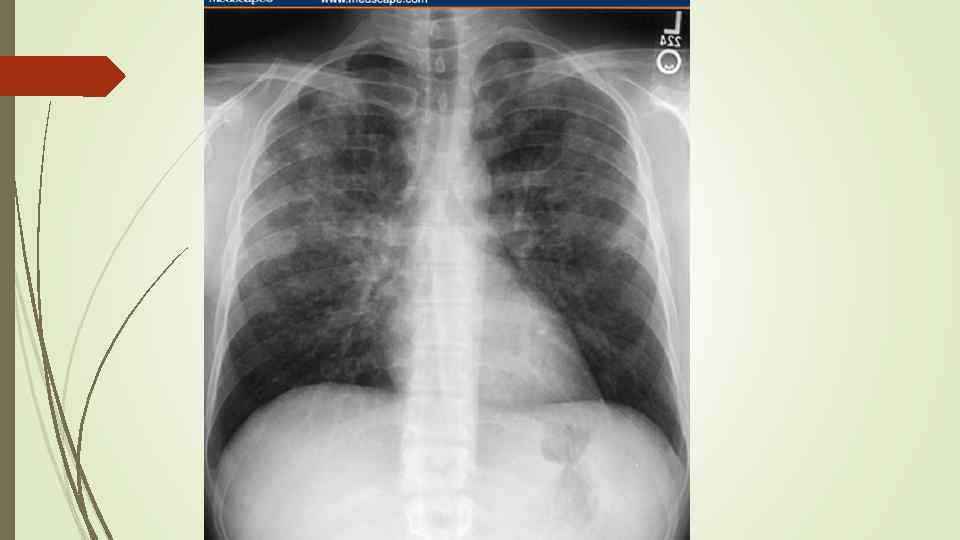

Бронхопневмония Характерно наличие двухсторонних множественных очаговых теней. Контуры очагов нечеткие, интенсивность тени небольшая. Инфильтрация неоднородна. Мелкие, малоинтенсивные очаги не всегда выявляются на снимках. Легочный рисунок усилен на всем протяжении легких. Корни расширены, не структурны. Как правило, отмечается реакция плевры, могут быть и экссудативные плевриты.

Бронхопневмония Характерно наличие двухсторонних множественных очаговых теней. Контуры очагов нечеткие, интенсивность тени небольшая. Инфильтрация неоднородна. Мелкие, малоинтенсивные очаги не всегда выявляются на снимках. Легочный рисунок усилен на всем протяжении легких. Корни расширены, не структурны. Как правило, отмечается реакция плевры, могут быть и экссудативные плевриты.

bronhopneumoni

bronhopneumoni